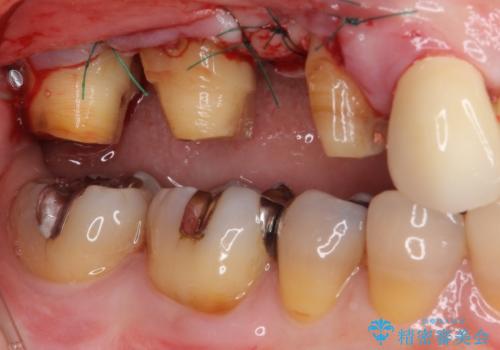

失われていた歯槽骨を、再生治療により可及的に改善させ、その1年後に歯周ポケットを除去するための歯周外科処置を行うこととしました。

処置後はオールセラミックブリッジにて補綴し、再発防止のために就寝時にナイトガード(マウスピース)を装着していただくこととしました。

歯槽骨の再生には1年ほどの待機期間を要し、その後のポケット除去処置も数か月の待機期間を必要とするため、治療期間は長期に及びました。

治療途中からマウスピースを装着していただくことで、歯槽骨の回復も順調に進みました。